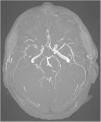

Primary central nervous system vasculitis. A rare disease with high mortality

Vasculitis primaria del sistema nervioso central. Una enfermedad rara con alta mortalidad